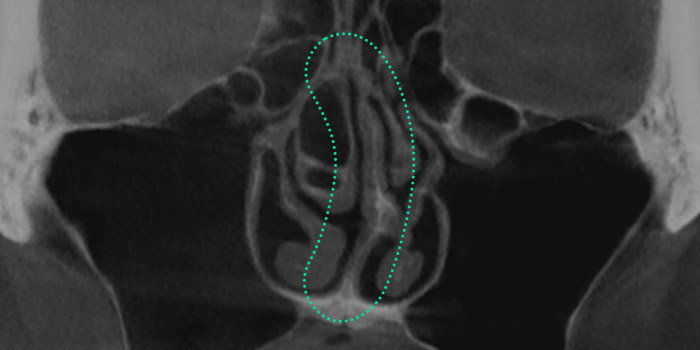

Crooked Nose Surgery is a procedure to straighten a deviated nose

caused by structural internal issues or trauma leading to asymmetry

of the bone or cartilage. Depending on the severity of the deviation,

a crooked nose can affect breathing, causing discomfort. Through

3D-CT scans, it is determined whether the deviation stems from

internal cartilage or is simply an external appearance issue. Accurate

diagnosis is essential, followed by a customized surgical approach

to properly correct the condition.

Crooked Nose Surgery is a procedure to straighten a

deviated nose by using 3D-CT to accurately diagnose

whether the cartilage inside is bent or if the deviation

is only visible externally, followed by a customized

surgical method tailored to the condition for proper

correction.

Septal Deviation

A condition where the septal cartilage,

which supports the center of the nose, is bent.

This can lead to functional impairments

such as nasal obstruction, rhinitis, and

sinusitis, and often causes visible nasal

bridge deviation.

When the cartilage located at the center of the nose

becomes bent, it can cause functional issues

such as nasal obstruction, rhinitis, and sinusitis.

Nasal Valve Stenosis

The nasal valve, located at the upper part

of the internal nose, regulates airflow.

When the septal cartilage is bent, it narrows

this passage, resulting in breathing difficulties and

nasal obstruction. This condition, known as nasal

valve stenosis, is more common in individuals

with a low nasal bridge.

Narrowing of the upper internal nasal area,

responsible for regulating airflow, leads to nasal

obstruction and sleep disorders.

A crooked nose often involves not only the visible appearance but also the internal nasal structure.

Common types, including C-shaped, S-shaped, and diagonally shaped deviations, often accompany functional issues like septal deviation or nasal

valve stenosis, requiring precise 3D-CT and nasal endoscopy examinations to determine the cause and apply tailored solutions.

A crooked nose often involves deviations in the internal

nasal structure, with common types including C-shaped,

S-shaped, and diagonally shaped forms, frequently

accompanied by functional issues ike septal

deviation or nasal valve stenosis, making it crucial to identify